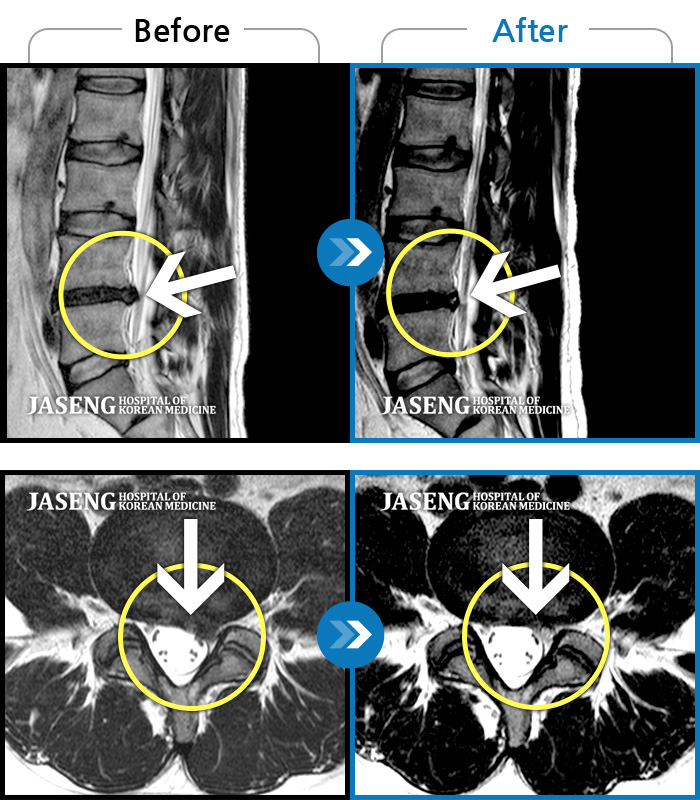

자생 비수술 한방통합치료 후

터진디스크가 흡수된 모습

Before

터진디스크 한방통합치료 전

After

터진디스크 한방통합치료 후

비수술 치료만으로

터진 디스크 흡수

튀어나온 디스크 대비,

터진 디스크 치료 효과 우수

디스크 흘러내린 정도가

심할수록 흡수 가능성 증가

치료 후 장기추적관찰 결과,

환자 90% 이상 치료 만족